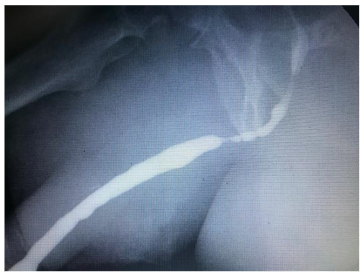

The urethral stent is a self-expanding steel mesh that opens the urethral lumen. It is a procedure under vision, outpatient, with little or no bleeding and does not require a urethral catheter, the patient urinates immediately after stent implantation. It can be considered as an alternative to the indwelling urethral catheter in selected patients with bladder outlet obstruction. It’s a very good option in elderly patients with benign prostatic hyperplasia, chronic retentionists and with high surgical risk with multiple pathologies and polypharmacy or who refuse surgery.